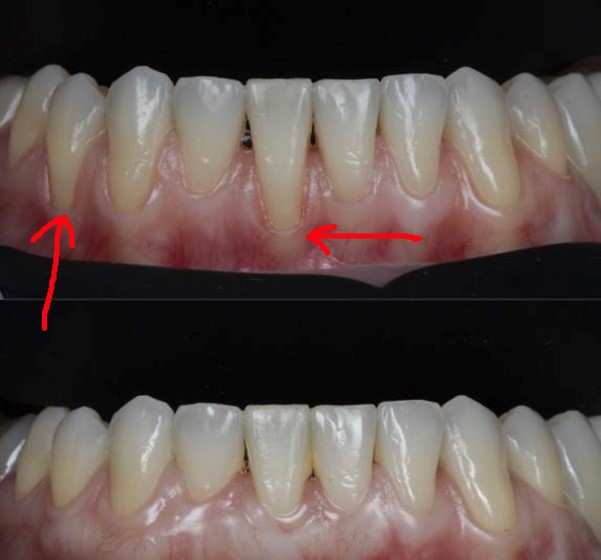

Вверху фото десны с рецессией до операции, а внизу — после операции

На начальных этапах, пока рецессия не дошла до тканей пародонта, вернуть всё к норме можно достаточно быстро, качественно и относительно дёшево. Если же десневые сосочки между зубами атрофировались, пересаживать лоскуты слизистой с нёба, чтобы нарастить десну, придётся гораздо дольше и дороже.